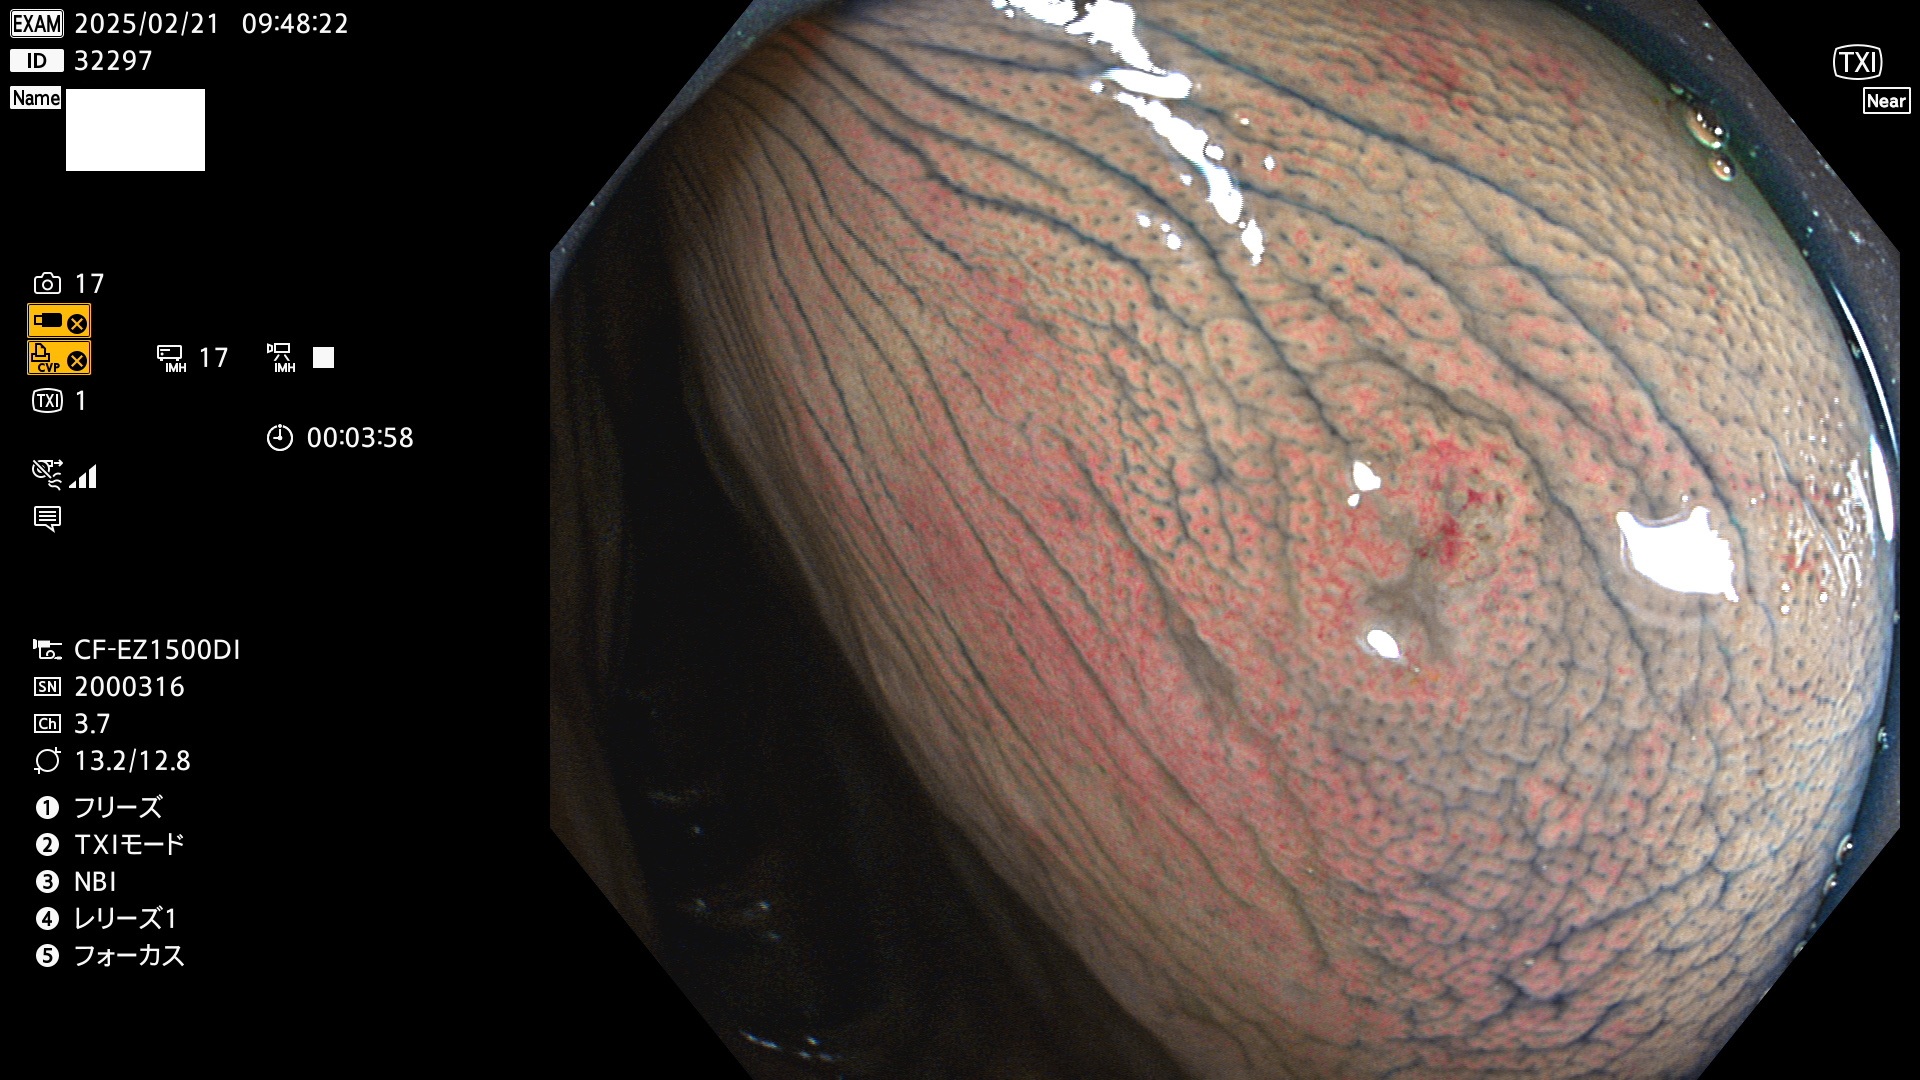

完全に平坦な物をUb、陥凹している物をUcと呼びます。最も発見が難しく危険な病変です。

毎週の検査(木・金・土・日)に発見されたUb、Uc型・腺腫を、その週の日曜の夜にUPし1週間、提示します。

抽出の対象期間 2025年2月20日〜2月23日の4日間(48件の検査)8個 (8/48=16%)